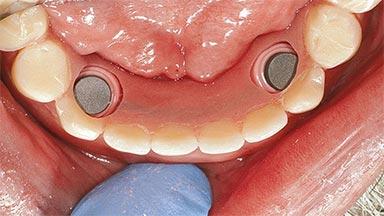

An 83-year-old man presented together with his caregiver at the dental department of the Medical University of Innsbruck, Austria with complaints of swelling in the right maxillary canine area and loss of retention of his 5-years-old mandibular denture. The patient had a significant medical history (20 years) of bipolar affective disorder with moderate depression (F 31.3) and dementia in Alzheimer’s disease (F 00.2). The patient had been in ambulant psychiatric therapy for his depressive illness for the past 20 years. He lived alone and had no children; his sister assisted with daily living. She reported that the patient exhibited compulsive hoarding behavior. In the previous two months, she had noted increasing disorientation and vertigo in the patient. She therefore accompanied him for a medical consultation at the Department of Psychiatry and Psychotherapy of the Medical University of Innsbruck. He was released home after a 6-week inpatient stay.

# of Implants 2

Type of Implants One-Piece

Attachment One-Piece

Defining Characteristics Fully edentulous lower jaw to be rehabilitated with an implant-borne removable overdenture

Loading Protocol Conventional/early